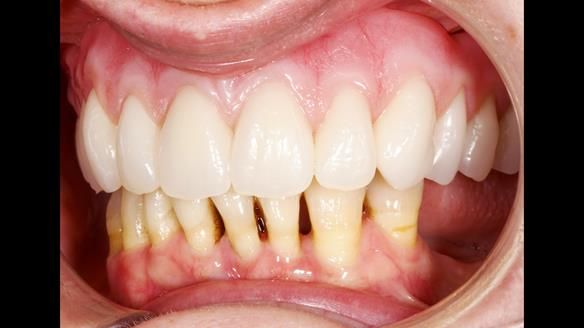

She had previously suffered from generalised periodontitis – stage IV, grade C, currently stable, with reduced attachment across the upper arch.

By the time she came to me, her periodontal condition was stable — but the aesthetics in the upper jaw were very poor.

We provided her with an immediate upper denture (Mk 1), followed by a definitive metal-based upper denture (Mk 2). A lower removable partial denture was discussed, to be made only if needed once the upper treatment was complete. However, at review, this wasn’t necessary — Adnana had excellent neuromuscular control and function, even with a shortened dental arch (SDA).

- Immediate denture (Mk 1) fitted the same day the teeth came out

- Definitive denture (Mk 2), metal-based and custom-designed for her face

- A restored smile, restored lip support, and a patient who owned the journey